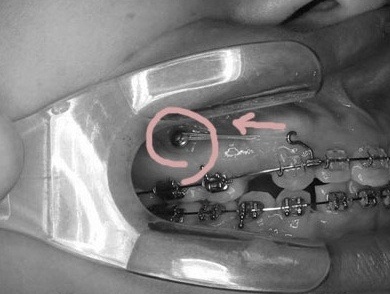

돌출치료에 쓰인 경우입니다. 어금니가 아닌 스크류로 앞니를 당겨서 입을 많이 집어넣습니다.

어금니로 당기면 어금니가 나오기 때문입니다.